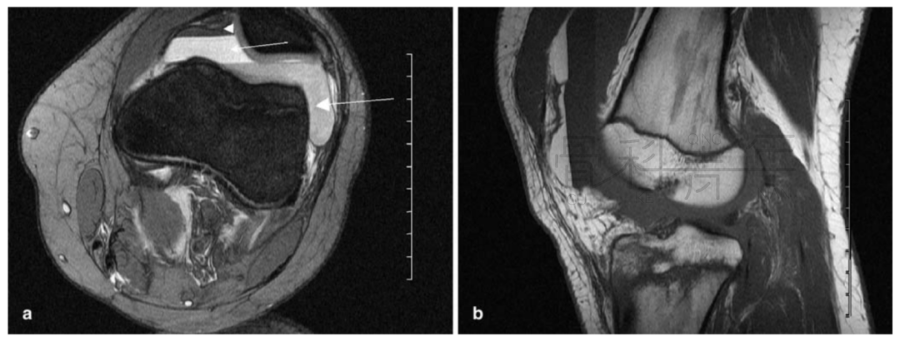

病例2一例左膝外伤患者。在MR横断与矢状位上均可见明显液体分层(见箭头所示)。